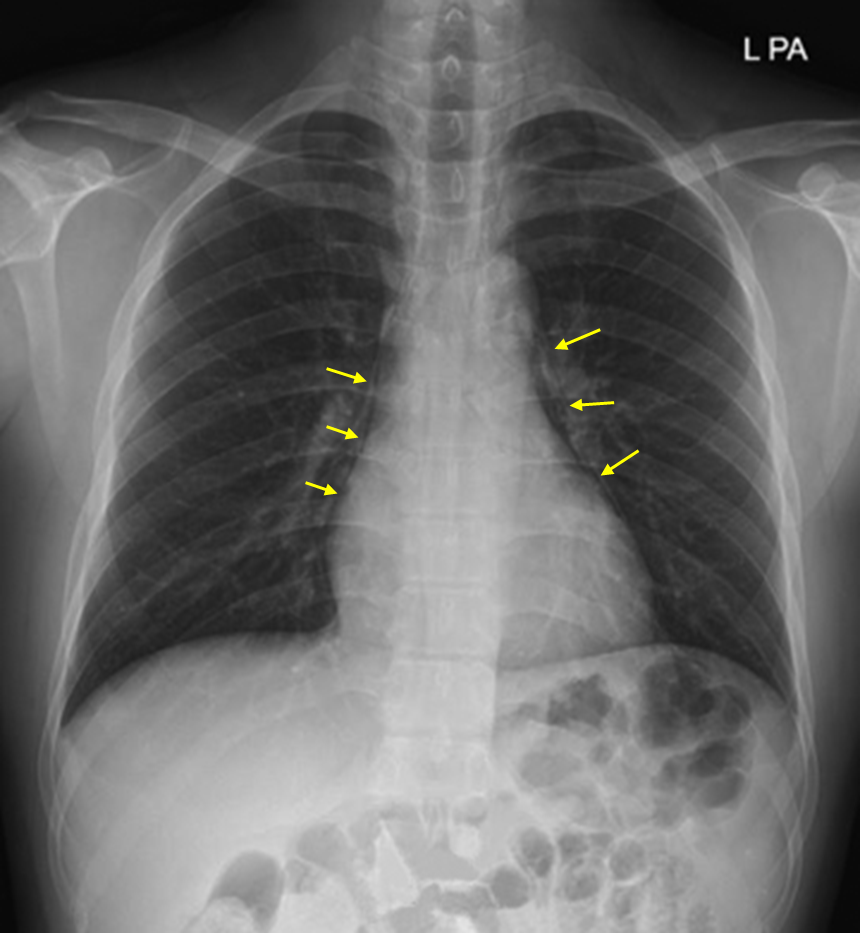

Img | CXR: Bilateral pleural line adjacent to mediastinum CT: Air inside mediastinum |

영상검사상 mediastinum 내 air가 관찰되므로 종격동기종으로 진단한다.

• CXR에서 심장 옆으로 얇은 pleural line이 보이며, CT에서도 종격동 내부에 air bubble이 관찰되므로 종격동기종으로 진단한다.